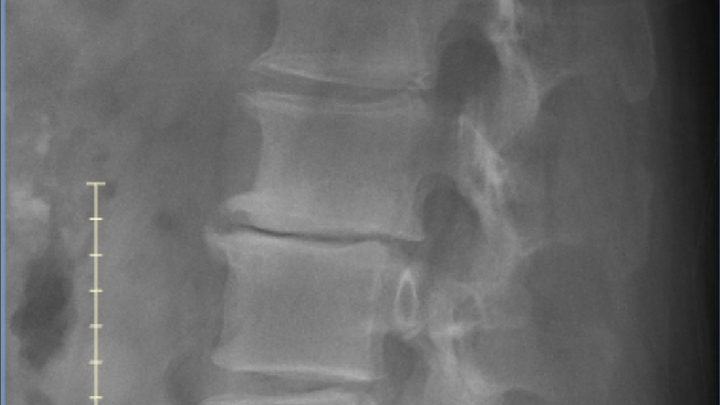

So, I was trying not to use this so much anymore. But, things have taken a turn for the worse. My surgeon had x-rays done on my lower back and they showed that two discs are almost completely gone and three others are close. So, I won't be cleared for work for the foreseeable future. I've only posted this from the beginning out of desperation and have only become more desperate. If you are able to help my appreciation would know no bounds.